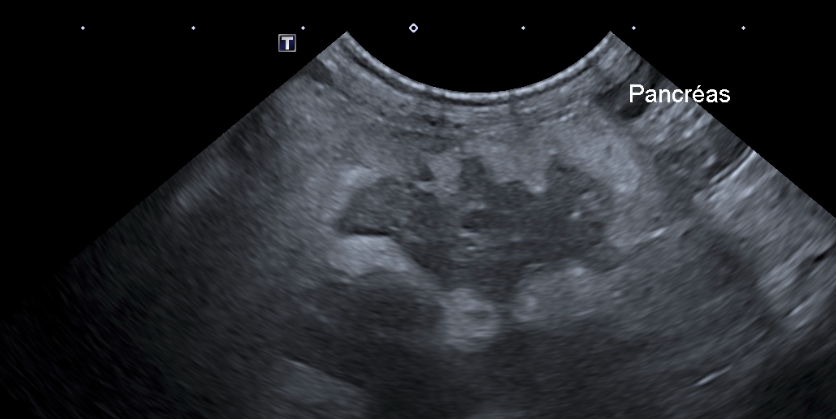

Jour 2 : Le pancréas, vaisseaux et nœuds lymphatiques tributaires.

• Rappeler l’écho anatomie du pancréas, des vaisseaux et des nœuds lymphatiques tributaires

• Savoir décrire les images anormales du pancréas, des vaisseaux et des nœuds lymphatiques tributaires

• TP d’échographie sur chiens

• Interpréter exercices dirigés de reconnaissance et description d’images normales et anormales du pancréas , des vaisseaux et des nœuds lymphatiques tributaires.